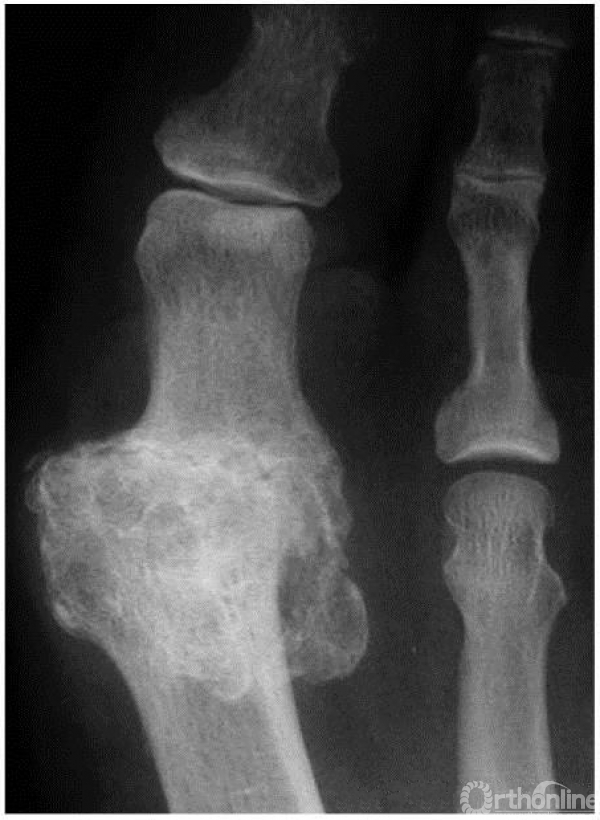

3期:正位X线上,关节间隙广泛变窄,籽骨形态不规则

4期:关节炎表现较3期更为明显、严重(3,4期影像学表现可以差别不大,但临床表现却相差很大)